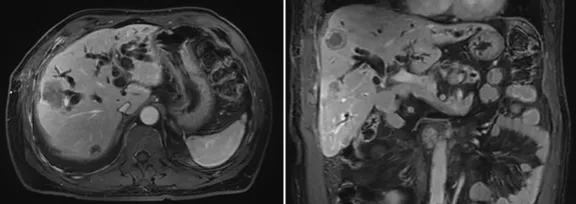

增強(qiáng)CT結(jié)果

壺腹部腺癌術(shù)后改變,左右肝管匯合部異常信號(hào),不除外復(fù)發(fā)可能;考慮肝內(nèi)多發(fā)轉(zhuǎn)移瘤形成

所見右側(cè)胸腔積液,右下肺片狀異常信號(hào),建議進(jìn)一步胸部檢查